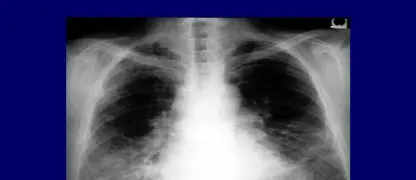

>>> Learn now: Bronchiectasis - Managing a chronic cough and lung infections

Image of the disease chronic sinusitis and other variables